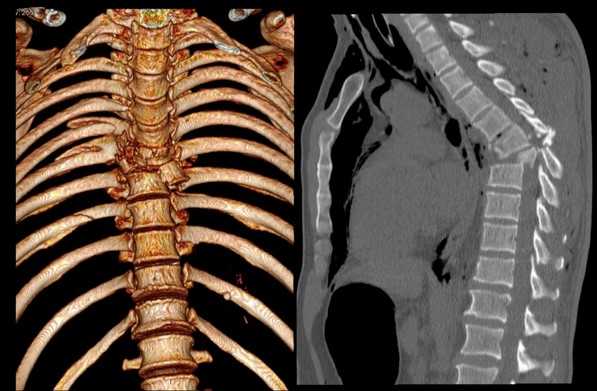

Перелом грудного отдела (трехмерная и сагиттальная проекции)

В результате компьютерной томографии получают серию послойных изображений рассматриваемой зоны. Монохромные фотографии обладают высоким разрешением. В отличие от рентгенографии на снимках отсутствуют дефекты и тени от расположенных рядом структур. Изменение плоскости при реконструкции изображений позволяет тщательно изучить анатомические образования. Преимуществом КТ является возможность создания 3D-модели позвоночника.

Компьютерная томография позвоночника показывает малейшие нарушения строения и функциональности суставных элементов. Трехмерное изображение при подготовке к хирургическому вмешательству позволяет локализовать патологический процесс, уточнить объем предстоящей операции.

Трехмерная реконструкция при КТ